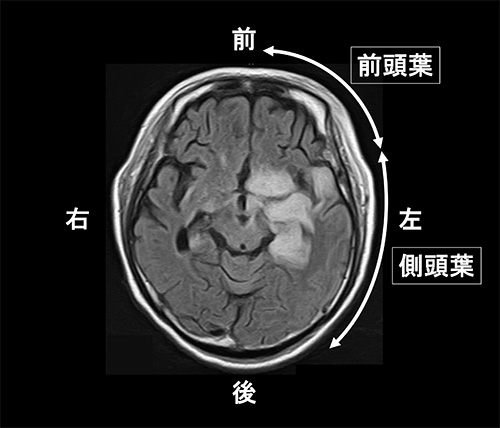

脳・脊髄・神経系の感染症について |